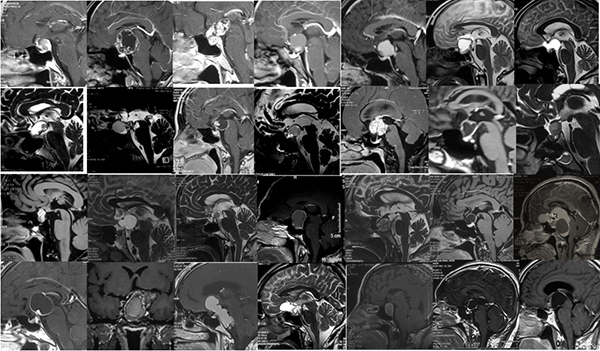

2018.12-2019.8   完成的100例听神经瘤手术